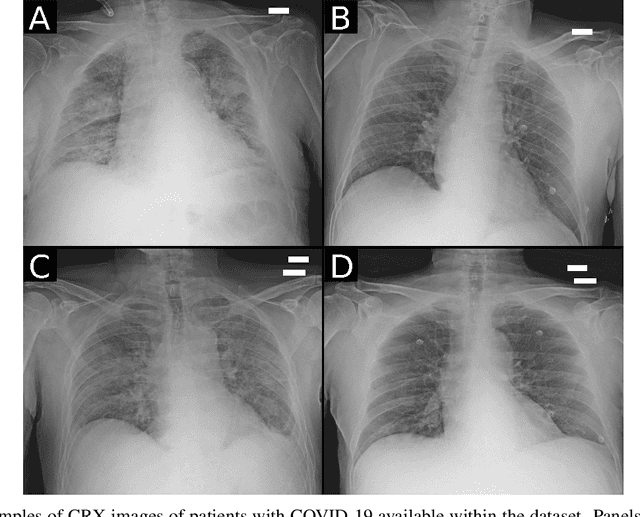

Abstract:Recent epidemiological data report that worldwide more than 53 million people have been infected by SARS-CoV-2, resulting in 1.3 million deaths. The disease has been spreading very rapidly and few months after the identification of the first infected, shortage of hospital resources quickly became a problem. In this work we investigate whether chest X-ray (CXR) can be used as a possible tool for the early identification of patients at risk of severe outcome, like intensive care or death. CXR is a radiological technique that compared to computed tomography (CT) it is simpler, faster, more widespread and it induces lower radiation dose. We present a dataset including data collected from 820 patients by six Italian hospitals in spring 2020 during the first COVID-19 emergency. The dataset includes CXR images, several clinical attributes and clinical outcomes. We investigate the potential of artificial intelligence to predict the prognosis of such patients, distinguishing between severe and mild cases, thus offering a baseline reference for other researchers and practitioners. To this goal, we present three approaches that use features extracted from CXR images, either handcrafted or automatically by convolutional neuronal networks, which are then integrated with the clinical data. Exhaustive evaluation shows promising performance both in 10-fold and leave-one-centre-out cross-validation, implying that clinical data and images have the potential to provide useful information for the management of patients and hospital resources.